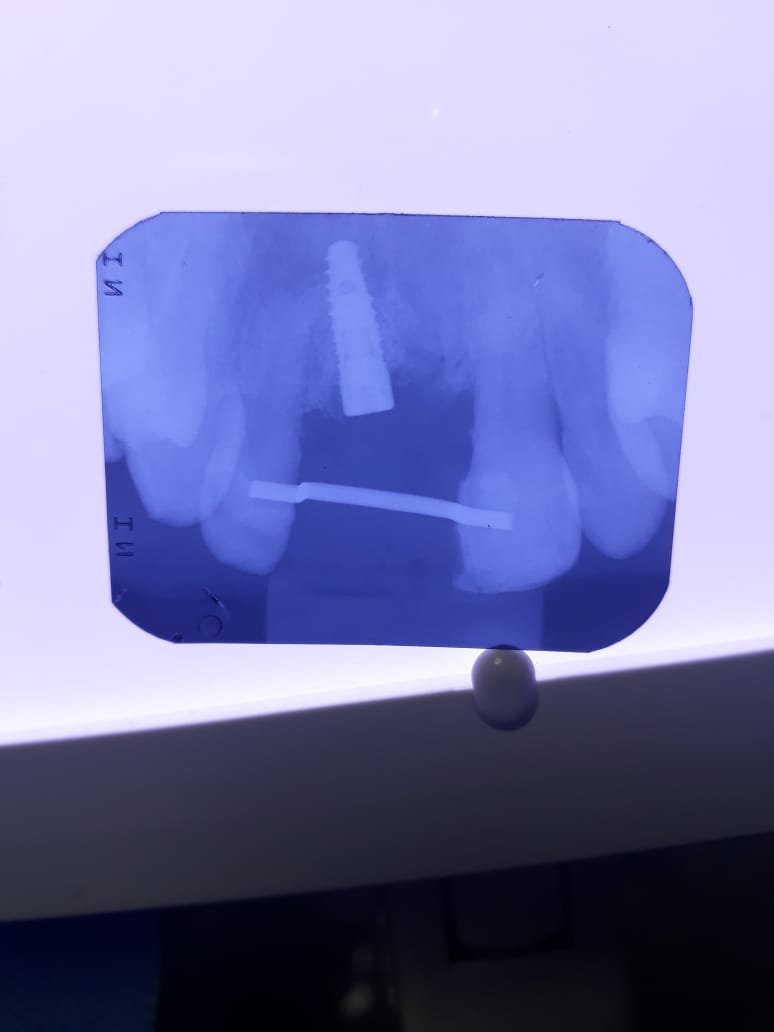

Hola, me ha venido un paciente sin piezas en el sector anterior y con dos implantes. La clínica suya esta cerrada y no sabe que implantes son. Necesito ayuda! [...]